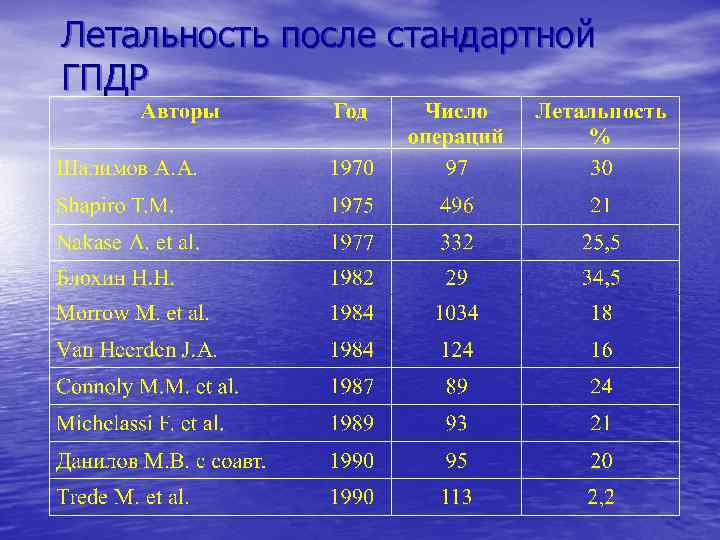

Летальность после стандартной ГПДР